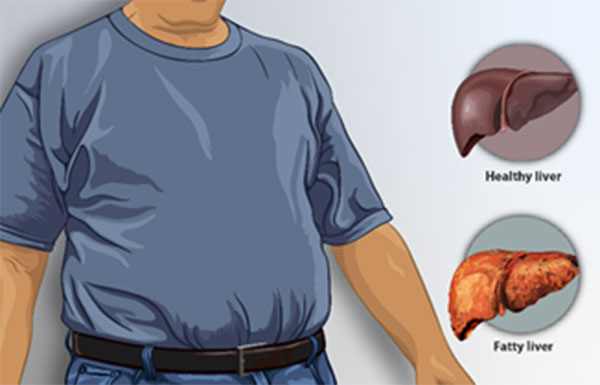

Non-Alcoholic Fatty Liver Disease is increasingly common worldwide and linked to obesity, diabetes, and metabolic syndrome. Recent research underscores that MASLD treatment centers on lifestyle modification and drug therapies targeted at metabolic risk factors.